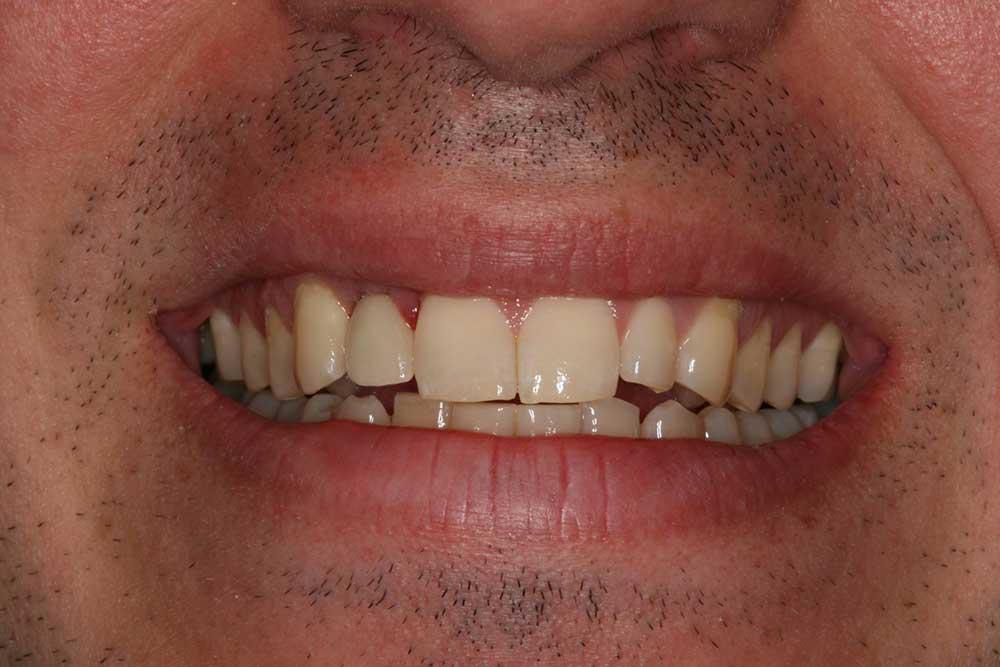

Anthony A.

This patient had only a few remaining infected teeth, but didn’t want to settle for just a denture.  Placed multiple implants and provided a secure fixed option which allowed him to not only chew better but to smile again.